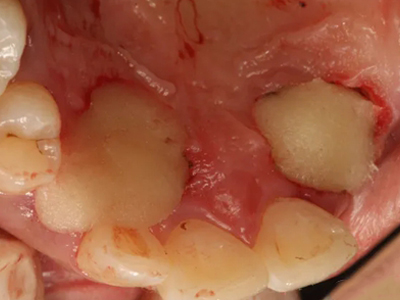

阻生牙可反复引起冠周炎,或引起邻牙牙根吸收和破坏,位置不正,不能完全萌出,好发部位是上、下颌第三磨牙。

对于阻生牙的处置需要首先明确阻生牙齿发育情况是否正常,对于由于早期外伤或其他原因造成发育异常,如牙根弯曲、短根等情况的阻生牙,还应根据患者的综合情况,决定牙齿是否保留。